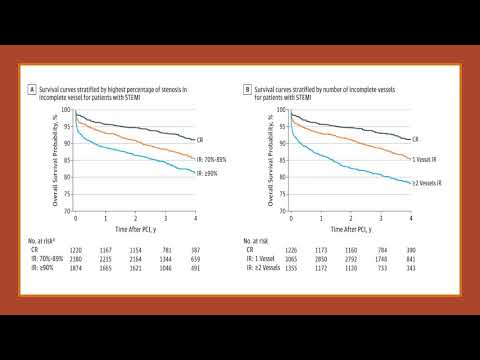

Características anatómicas de las coronarias y revascularización incompleta. Dra. Ana Laura Mori. Residencia de Cardiología. Hospital C. Argerich. Buenos Aires